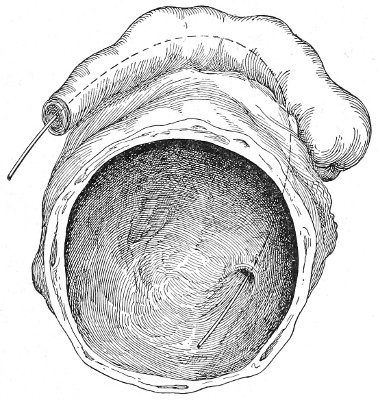

The Sims position, which is also called the latero-abdominal position, is shown in Fig. 10. The woman is placed on the bed or table upon her left side. The side of the face is upon the pillow; the left arm is behind the back, so that the left breast rests upon the table. The thighs are flexed upon the abdomen at an angle of about 90° to the trunk. The right thigh is more flexed than the left, so that the right knee may touch the table above the left knee. The legs are flexed on the thighs. In this position there is a tendency for the intestines, following the force of gravity, to fall from the pelvis, 32 and for the uterus and other pelvic viscera to be drawn up. When the perineum is retracted with the blade of the Sims speculum, air will enter the vagina and the vaginal slit will become distended (Fig. 11). To facilitate inspection of the cervix it is usually necessary also to push forward the anterior abdominal wall by some kind of depressor, such as the one shown in Fig. 8.

Fig. 11.—The cervix uteri exposed with the Sims speculum.